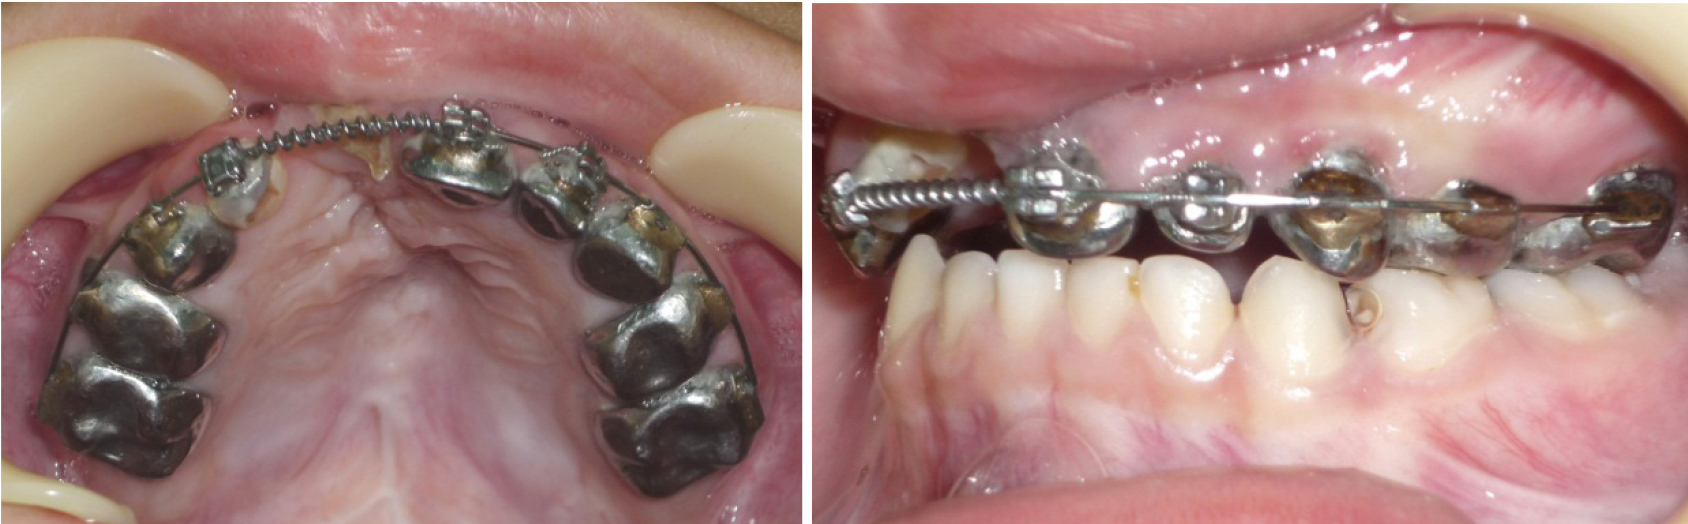

Эффективность предложенных методов графического построения прогнозируемых форм зубных арок определялась при анализе результатов лечения детей с врожденной аномалией в периоде молочного прикуса. С этой целью проведено лечение 15 детей с врожденным односторонним несращением губы и нёба. Практически во всех клинических случаях определялось сужение трансверсальных размеров, более выраженное в переднем сегменте арки. Окклюзия не соответствовала признакам физиологической нормы. Отмечалось укорочение глубины арки (рис. 2).

Лечение проводилось с применением несъемной дуговой аппаратуры. Фиксирующими элементами служили тонкостенные коронки (кольца) с припаянными вестибулярными брекетами. Размер металлической дуги определяли с помощью предложенных методов графического анализа (рис. 3). Металлические дуги меняли с учетом протокола лечения эджуайс-техникой до нормализации формы арки, соответствующей прогнозируемым размерам. После нормализации окклюзионных взаимоотношений аппарат использовался в качестве ретенционного до смены молочных зубов постоянными (рис. 4).